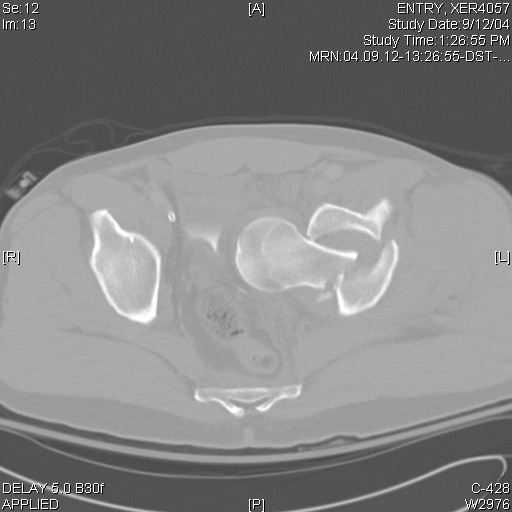

Intrapelvic farcture dislocation of the hip

Anyone ever seen one like this before? Any suggestions on how to get that thing out of there, because I tried and couldn't

-got called in to the OR by a colleague with the patient already on the fracture table and 2 big incisions (lateral and iliac crest) already made. Gave up after an hour or two and will try again if I can figure the solution.